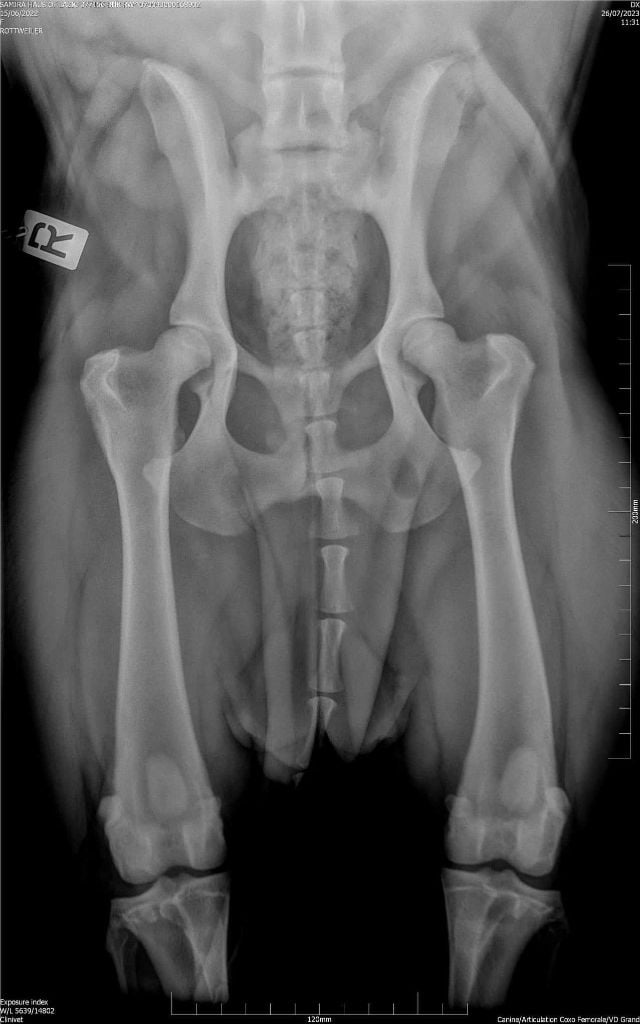

RADIO OFFICIELLE HANCHES

ADN : FAIT DYSPLASIE COUDES : ED0 DYSPLASIE HANCHES : HDA JLPP : CLEAR |